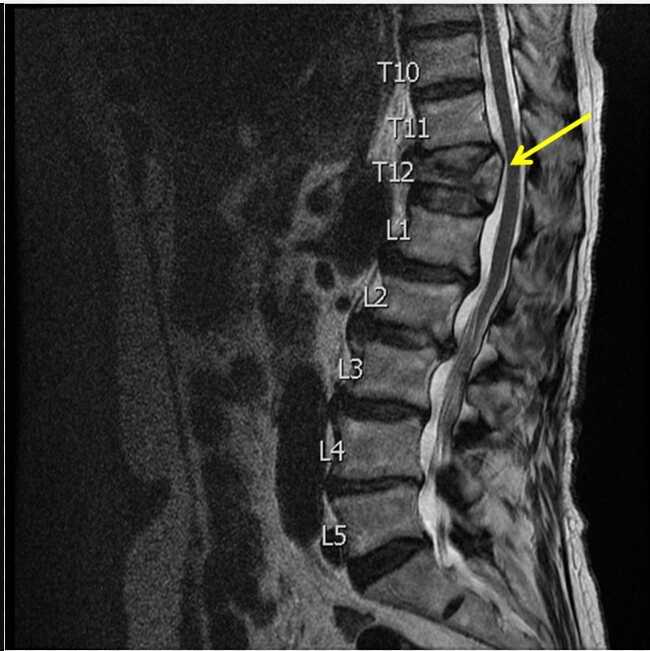

Based on this image, does this patient have an old or a new fracture?

new fracture (black is whack, white is right)

Based on this image, does this patient have a new or old fracture?

old fracture (black is whack, white is right)